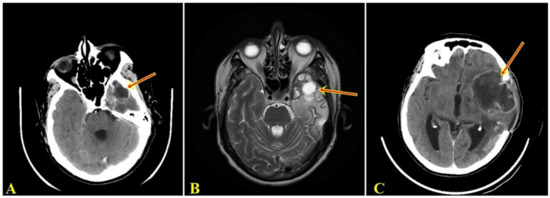

2. Case

2.1. Clinical Summary